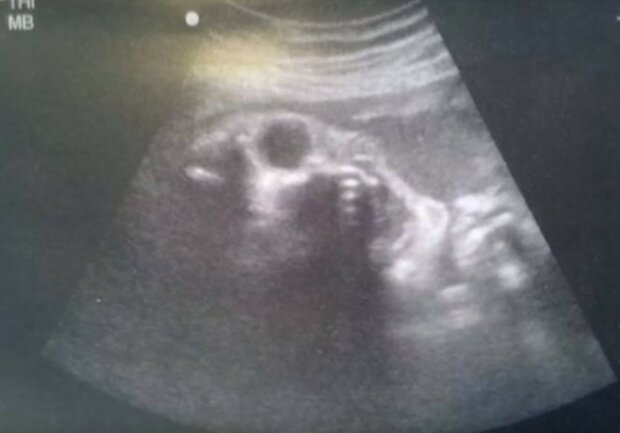

To, co tito rodiče uviděli na ultrazvuku, nelze stoprocentně racionálně vysvětlit. Během běžného ultrazvukového vyšetření se objevily znepokojivé a chvílemi děsivé snímky. Šlo o technickou závadu nebo zlou tvář?

Ultrazvuk nám občas ukáže něco, co bychom nikdy v životě nečekali. Těžko říct, zda jde o závadu nebo naši fantazii, ale to, co je na těch snímcích, může budoucí rodiče vyděsit.

Zjevuje se démonická tvář, jako by strnula ve výkřiku.

Zdeformovaná tvářička, výsledek závady, nebo něco velmi temného?

Zvláštní chrup a otevřená pusa, jako křičící démon...